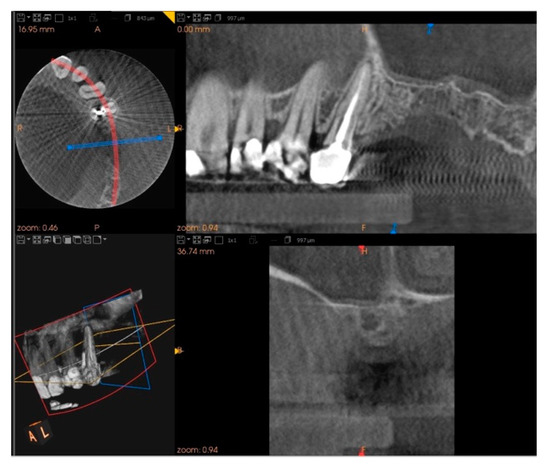

Five months after the extraction, a cone-beam computed tomography (CBCT) was also performed to design the implant insertion. The radiological examination showed bone volume preservation of the post-extraction site and no signs of osteonecrosis (Figure 9 and Figure 10).

Figure 9.

Cone-beam computed tomography (CBCT) shows bone volume preservation in the mesial surface of the alveolus.

Figure 10.

Cone-beam computed tomography (CBCT) shows bone volume preservation in the distal surface of the alveolus.